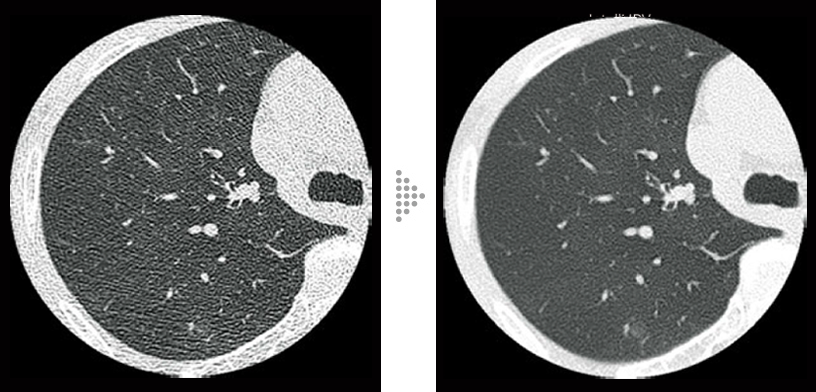

FBP(izquierda)

Intelli IPV(derecha)